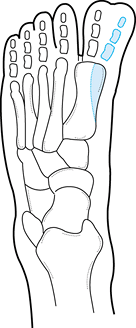

the Coleman block test (Fig. 167.9). This test

differentiates between rigid varus, which must be surgically treated by

triple arthrodesis, and varus secondary to first metatarsal depression,

which is flexible and corrects once the medial column cavus has been

corrected using midfoot dorsal wedge osteotomy.

![]() |

|

Figure 167.9. Coleman block test. A block is placed beneath the heel and the fifth metatarsal head while the patient stands. A: The heel varus corrects, indicating hindfoot flexibility. B: Heel varus persists, indicating hindfoot rigidity.